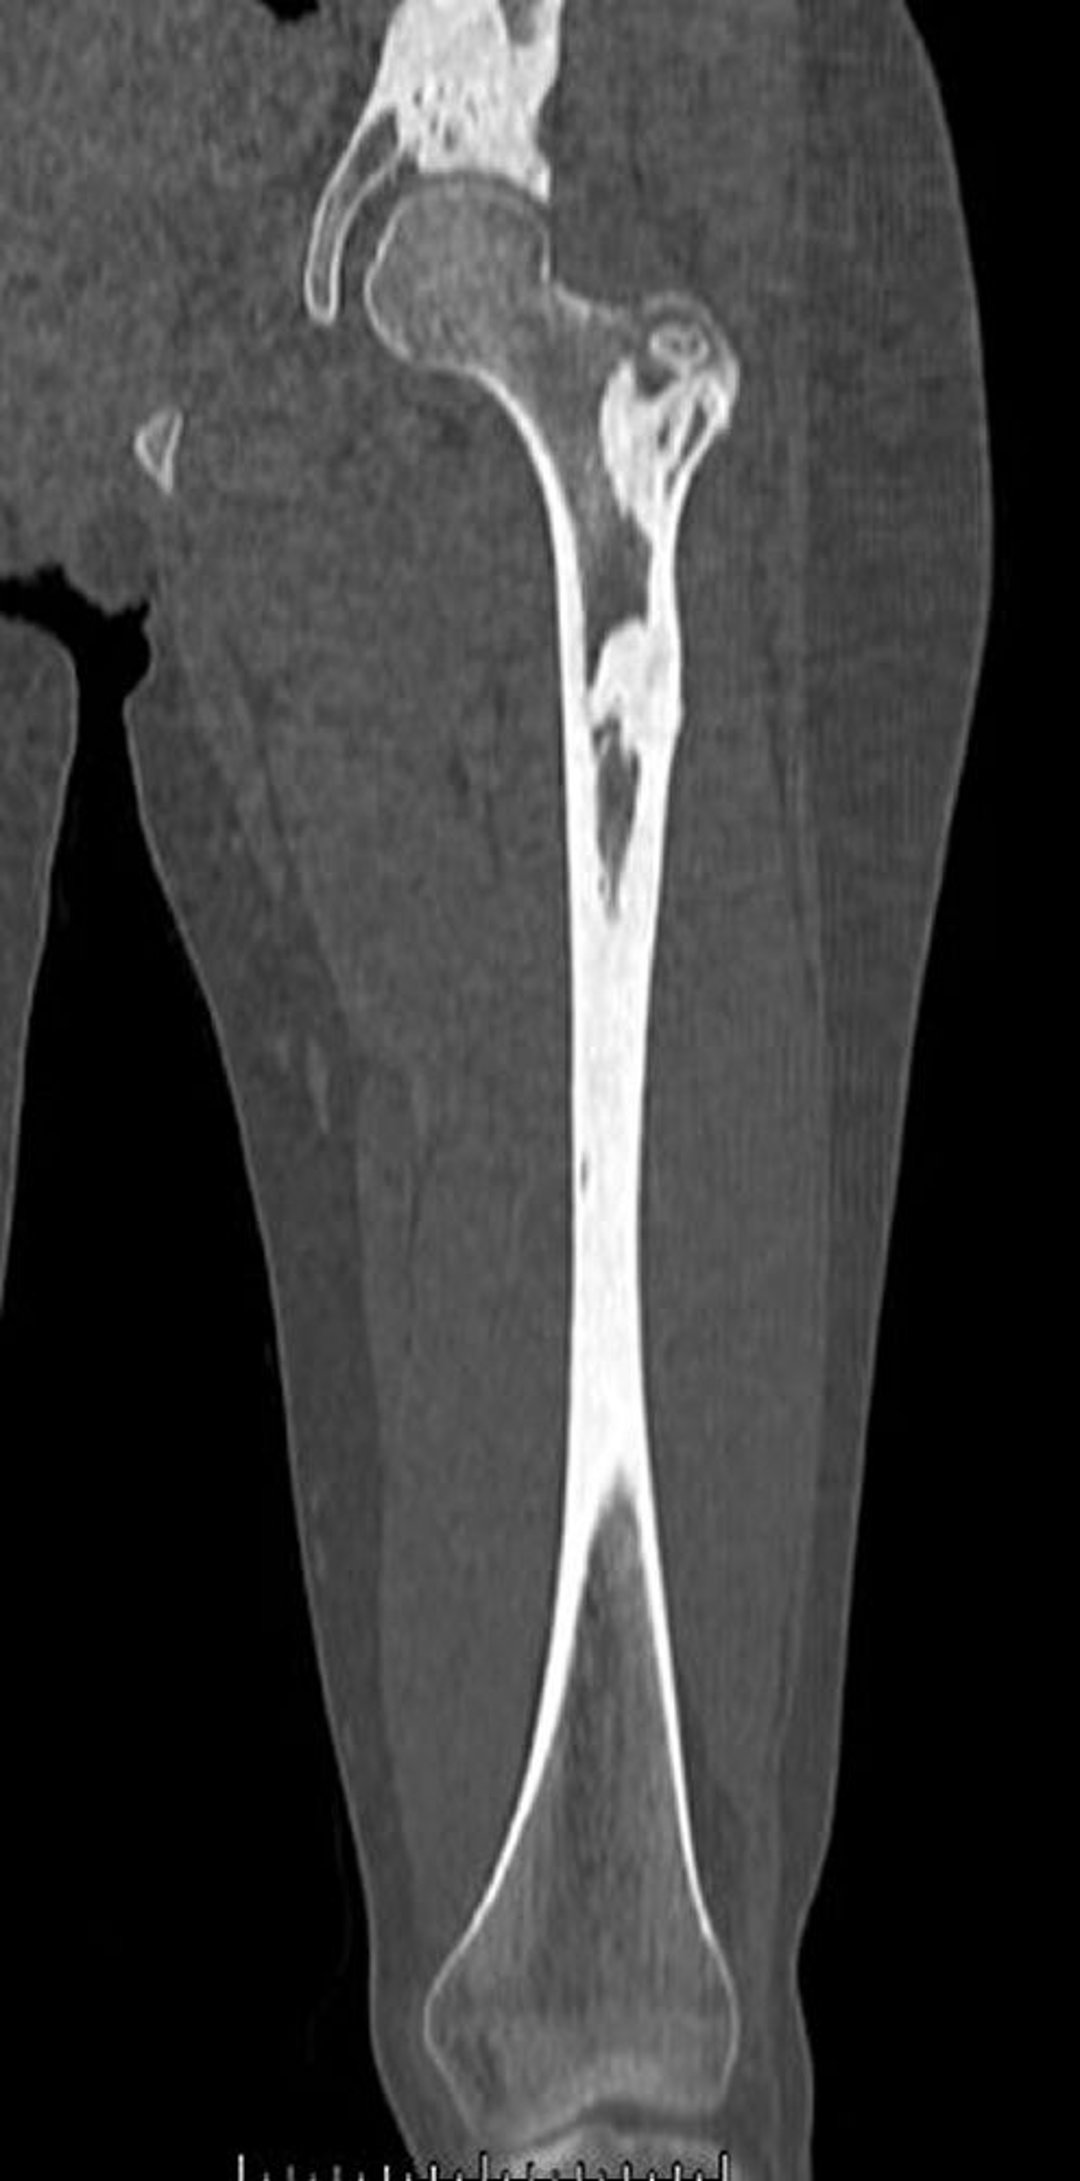

Bệnh nến xương (chụp CT)

Hình ảnh chụp CT này cho thấy các tổn thương xương dày đặc của bệnh nến xương ở xương đùi và xương chậu.

Hình ảnh do bác sĩ Michael J. Joyce và bác sĩ David M. Joyce cung cấp.